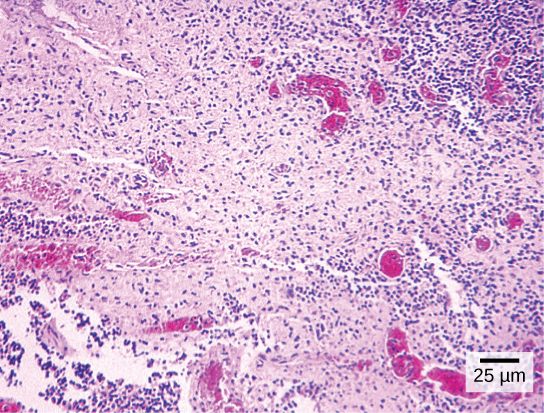

Most student microscopes are classified as light microscopes (Figure 1a). Visible light both passes through and is bent by the lens system to enable the user to see the specimen. Light microscopes are advantageous for viewing living organisms, but since individual cells are generally transparent, their components are not distinguishable unless they are colored with special stains. Staining, however, usually kills the cells.

Light microscopes commonly used in the undergraduate college laboratory magnify up to approximately 400 times. Two parameters that are important in microscopy are magnification and resolving power. Magnification is the degree of enlargement of an object. Resolving power is the ability of a microscope to allow the eye to distinguish two adjacent structures as separate; the higher the resolution, the closer those two objects can be, and the better the clarity and detail of the image. When oil immersion lenses are used, magnification is usually increased to 1,000 times for the study of smaller cells, like most prokaryotic cells. Because light entering a specimen from below is focused onto the eye of an observer, the specimen can be viewed using light microscopy. For this reason, for light to pass through a specimen, the sample must be thin or translucent.